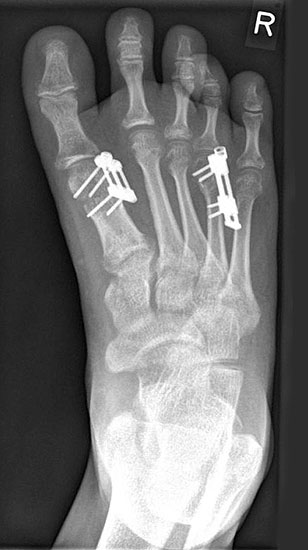

Das im Folgenden vorgestellte Operationsverfahren beschreibt die Kallusdistraktion von Metatarsalia nach den Prinzipien von Ilisarov 21 unter Verwendung eines internen, winkelstabilen Titan-Minifixateur (Klauser 2009). Der interne Distraktor ermöglicht während der Distraktions- und der Durchbauungsphase aufgrund seiner hohen Stabilität je nach Modell (18 mm, 23 mm) eine Verlängerung von bis zu 25 mm. Nach interner Anlage des Minifixateurs, meist lateral, kann über eine kontinuierliche Kallusdistraktion der Metatarsalebogen unter frühzeitiger Mobilisation im Gips oder Short-Walker rekonstruiert werden 15. Über einen interdigital und transcutan ausgeleiteten Aktivatorstab wird die Distraktion vom Patienten selber täglich morgens und abends durchgeführt. Zusätzlich vorliegende Strahlpathologien, wie zum Beispiel eine verkürzte Strecksehne oder ein kontraktes Metatarsophalangealgelenk können im Rahmen der Erstoperation ebenso therapiert werden wie z.B. ein Hallux valgus, ein Hallux valgus interphalangeus und/oder ein Digitus quintus varus (Klauser 2009). Nach Rekonstruktion des Metatarsalebogens wird in einem zweiten, kleinen Eingriff der Aktivatorstab über eine Spezialpinzette diskonnektiert und entfernt, wobei der Distraktor als interne Fixation belassen wird. Die Entfernung des Distraktors erfolgt in der Regel nach 9 – 12 Monaten, da es sich meist um angeborene kindliche Fehlbildungen handelt (Brachymetatarsie) und eine operative Intervention frühzeitig im Kindesalter erfolgen sollte (Klauser 2009).

• Simultane Behandlung eines doppelstrahligen longitudinalen Reduktionsdefektes möglich 113 (Klauser 2009).

Meist kam ein 18mm Minifixateur zur Anwendung und ausnahmslos wurde er lateral am Metatarsale implantiert. Bis auf das Metatarsale 5 wurden vom Autor alle weiteren Metatarsalia (MT1 – MT4) isoliert oder kombiniert verlängert. In 7 Fällen wurde eine simultane Verlängerung zweier Metatarsalia (2x MT1 und MT4, 4x MT3 und MT4, 1x MT2 und MT3) vorgenommen. Bei einem Großteil der Patienten musste eine Strecksehnenverlängerung entweder im Rahmen der Erstoperation oder im Rahmen der Aktivatorentkopplung vorgenommen werden. In neun Fällen (ausnahmslos bei Erwachsenen > 30 Jahre) sogar 2x sowohl während des Erst- als auch Zweiteingriffes. Annähernd regelhaft sind bei den eben genannten Eingriffen Arthrolysen des Metatarsophalangealgelenks des betroffenen Zehenstrahls erforderlich, da durch die Distraktionsverlängerung eine hohe Kompression auf das jeweilige Grundgelenk entsteht.